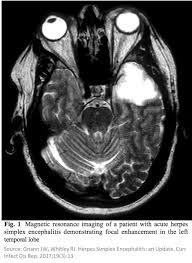

Mri is the imaging of choice in suspected cases of viral encephalitis, although ct scanning may be used where mri facilities are not available. A case of granulomatous hsv encephalitis: Hsv pcr and other infectious studies from the serum and csf were negative. Brain mri is shown in fig. Severe infection, particularly untreated herpes simplex virus (hsv) encephalitis, can cause brain hemorrhagic necrosis.

Brain mri—increased t2 signal intensity in frontotemporal region → viral (hsv) encephalitis.

In children older than 3 months and in adults brain biopsy: Herpesviral encephalitis, or herpes simplex encephalitis (hse), is encephalitis due to herpes simplex virus. • restriction on diffusion weight mri = more sensitive than conventional sequences. Misra uk, hashmi aa, kalita j. Diagnostic uncertainty and empirical management in pcr negative encephalitis. It is a severe condition brain mri may show limbic encephalitis (55) or diffuse t2 and dwi hyperintensities in the white matter, associated with restricted diffusion (54). Herpes simplex encephalitis occurs as 2 distinct entities: Mri is the imaging of choice in suspected cases of viral encephalitis, although ct scanning may be used where mri facilities are not available. The patient had initially improved after medical treatment. Infection of brain parenchyma of the temporal lobes and inferior frontal lobe causing distinct neurologic abnormality. Dhawan a, kecskes z, jyoti r, kent al. Associated with hsv encephalitis (strong evidence). In addition, because of the involvement of the.

It is a severe condition brain mri may show limbic encephalitis (55) or diffuse t2 and dwi hyperintensities in the white matter, associated with restricted diffusion (54). Brain mri—increased t2 signal intensity in frontotemporal region → viral (hsv) encephalitis. Associated with hsv encephalitis (strong evidence). Provided cranial imaging has excluded any contraindications such as a space occupying lesion or severe cerebral oedema and brain shift, a csf. Having said that, mri with contrast is considered the most sensitive imaging modality, and findings are present in over half of individuals 8. In addition, because of the involvement of the. We performed volumetric measurements of the left and right temporal lobes and of cerebral oedema. Herpes simplex encephalitis occurs as 2 distinct entities: The study analysed serially acquired magnetic resonance images (mri), of patients with acute hsv encephalitis who had neuroimaging repeated within four weeks of the first scan. Pregnancy the most common cause of encephalitis in newborns is vaginal delivery from a mother who is infected with herpes simplex virus 2 (hsv 2). There is no particular age, sex, or seasonal predilection. Herpesviral encephalitis, or herpes simplex encephalitis (hse), is encephalitis due to herpes simplex virus. Severe infection, particularly untreated herpes simplex virus (hsv) encephalitis, can cause brain hemorrhagic necrosis.